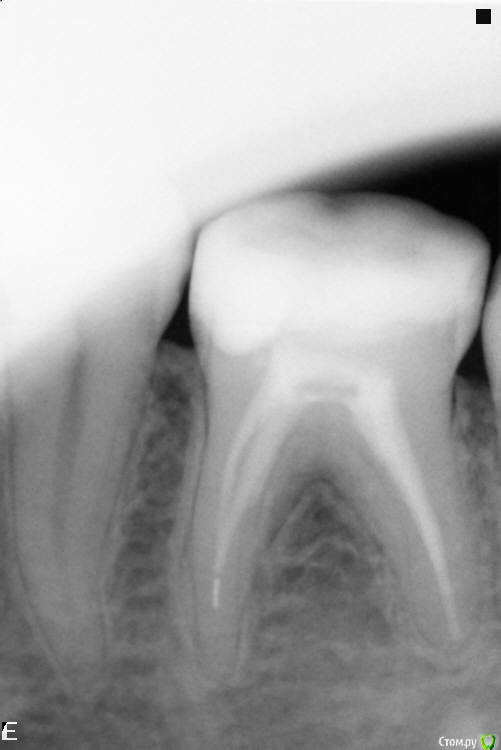

Зуб с отломком инструмента в канале, нужны рекомендации.

Описываю проблему: 36 зуб, в 2007 году был депульпирован под анестезией, без девитализации. 4 канала, запломбированы гуттаперчей. То, что каналов 4, хорошо помню - врач в процессе работы  показывал в зеркальце вставленные в каналы металлические штифты. Через полгода в другой клинике при лечении других зубов заодно  была заменена пломба и на этом зубе, из эстетических соображений, без вскрытия каналов. Перед заменой пломбы сделали рентген и показали на экране, что предыдущий стоматолог отломил в канале инструмент.  Восемь лет зуб вел себя примерно как живой - сохранялась температурная чувствительность и чувствительность к касанию и постукиванию. Две недели назад  зуб начал ощутимо болеть, особенно к вечеру - стоматолог диагностировал кариес под пломбой, заменил пломбу и отметил, что вообще-то зуб болеть не должен. К другим зубам претензий у врача не оказалось - остальные зубы либо совсем здоровы, либо качественно пломбированы.  26 зуб удален в 2001 году, через 4 года после депульпирования - при внешнем нормальном состоянии на рентене половина лица с левой стороны краснела и слегка опухала на несколько часов после пребывания зимой вне теплых помещений.

Сегодня посетил стоматолога повторно, по моей просьбе сделали прицельный снимок 36 зуба, пригласили для консультации хирурга и в общем-то, развели руками - зуб болеть не должен - на снимке не увидели ничего криминального. Тем не менее, зуб чувствителен к постукиванию и надавливанию, при вдыхании воздуха ртом или при полоскании полости рта водой комнатной температуры возникают умеренно болезненные ощущения.

Снимок зуба, сделанный сегодня, прикрепляю в исходном размере, каким мне его  записали на диск.

post-45548-0-45338800-1448292660_thumb.jpg

Каналы запломбированы не идеально, и в одном из них действительно есть отломок инструмента, но воспалительного процесса нет.